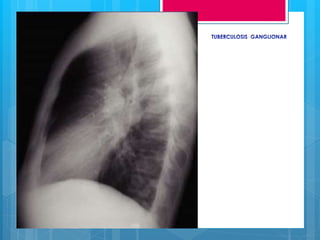

RX DE TÓRAX EN PACIENTE

TUBERCULOSO

 Frecuencia de falsos negativos es de 1%,

7-15% en pacientes HIV positivos.

 Dependen de factores del huésped:

edad, inmunosupresión, TB previa y varían

en la TB primaria y extra primaria

HALLAZGOS RADIOLÓGICOS EN TB PRIMARIA

 1- Linfadenopatía hilares

 2- Opacidades parenquimatosas de espacio aéreo

 3.Opacidades parenquimatosas del intersticio

 4. Enfermedad traqueobronquial

 5. Derrame pleural